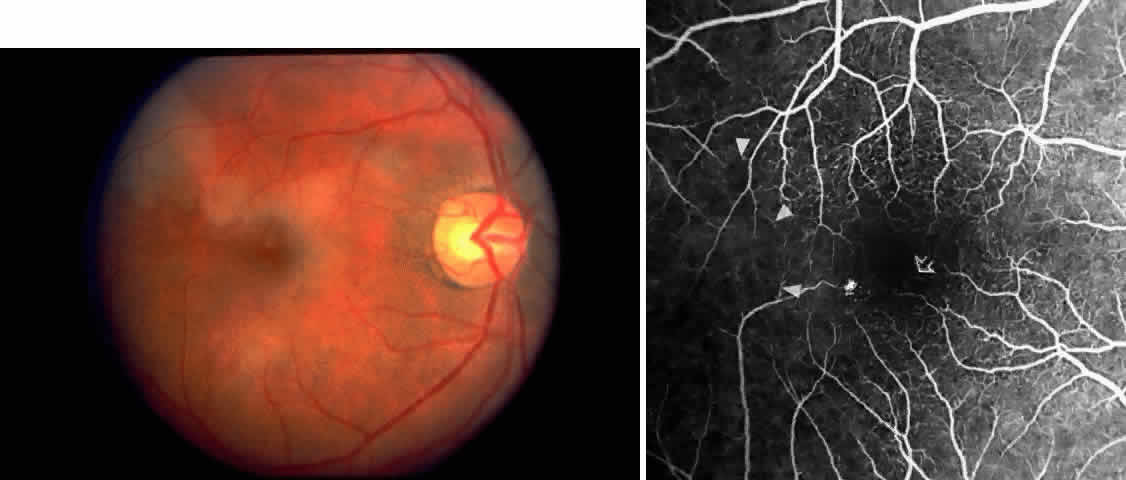

Macular Small Vessel Occlusions

Occlusions of the fine vasculature of the macular and perimacular area have been reported in 10% to 40% of patients with sickle cell disease.18,83,91–99 In the acute phase, the occluded vessel will have a dark red appearance and may appear as a dark line on fluorescein angiography (Fig. 9). Nerve fiber layer infarcts (cotton-wool spots) are seen (see Fig. 8D and E;Fig. 10).100

Other macular and perimacular changes include microaneurysm-like dots, dark and enlarged segments of arterioles, hairpin-shaped venular loops, pathologic avascular zones, and widening and irregularities of the foveal avascular zone (Figs. 11 and 12). In the Jamaican cohort study evaluating children with homozygous sickle cell anemia and SC disease between the ages of 5.0 and 7.5 years of age, no pathologic avascular zones could be identified despite a high incidence of peripheral vascular closure.31 In evaluating patients with homozygous sickle cell anemia, no relationship between ISC counts and macular abnormalities or visual acuity could be found.101 Using fluorescein angiography, investigators have found the foveal avascular zone to be significantly larger in eyes with clinical evidence of sickle cell maculopathy as compared with normal eyes and eyes without clinical evidence of sickle cell maculopathy.102–104

Careful examination by fluorescein angiography, looking for areas of capillary dropout and other capillary abnormalities, is often necessary to identify the macular changes. These changes may be transient, and the macula may appear normal on subsequent fluorescein angiograms (Fig. 13). Although fluorescein angiography may or may not demonstrate reperfusion of a previously occluded capillary bed, a loss of the inner retinal layers results in an ophthalmoscopic focal concavity with an abnormal reflex (retinal depression sign) (see Fig. 8E).105,106 These changes are usually permanent. The retinal depression sign is not pathognomonic of sickle cell disease and may be seen with other arteriolar occlusive diseases, such as embolic retinopathy, vasculitis, and hypertension.